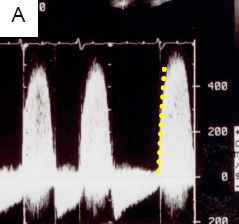

Figure 11.64 : Images ETO d’insuffisance mitrale sur dégénérescence myxoïde. A : excès de tissu avec ballonnisation, épaissisement localisé et prolapsus des deux feuillets ; la flèche indique le déplacement de l’extrémité des feuillets en arrière du plan de l’anneau mitral (trait pointillé). B : prolapsus isolé de P2. C : prolapsus de P2 avec rupture de cordage (indiqué par la flèche). D : rupture complète de muscle papillaire avec fragment de pilier attaché à l’extrémité du feuillet antérieur.